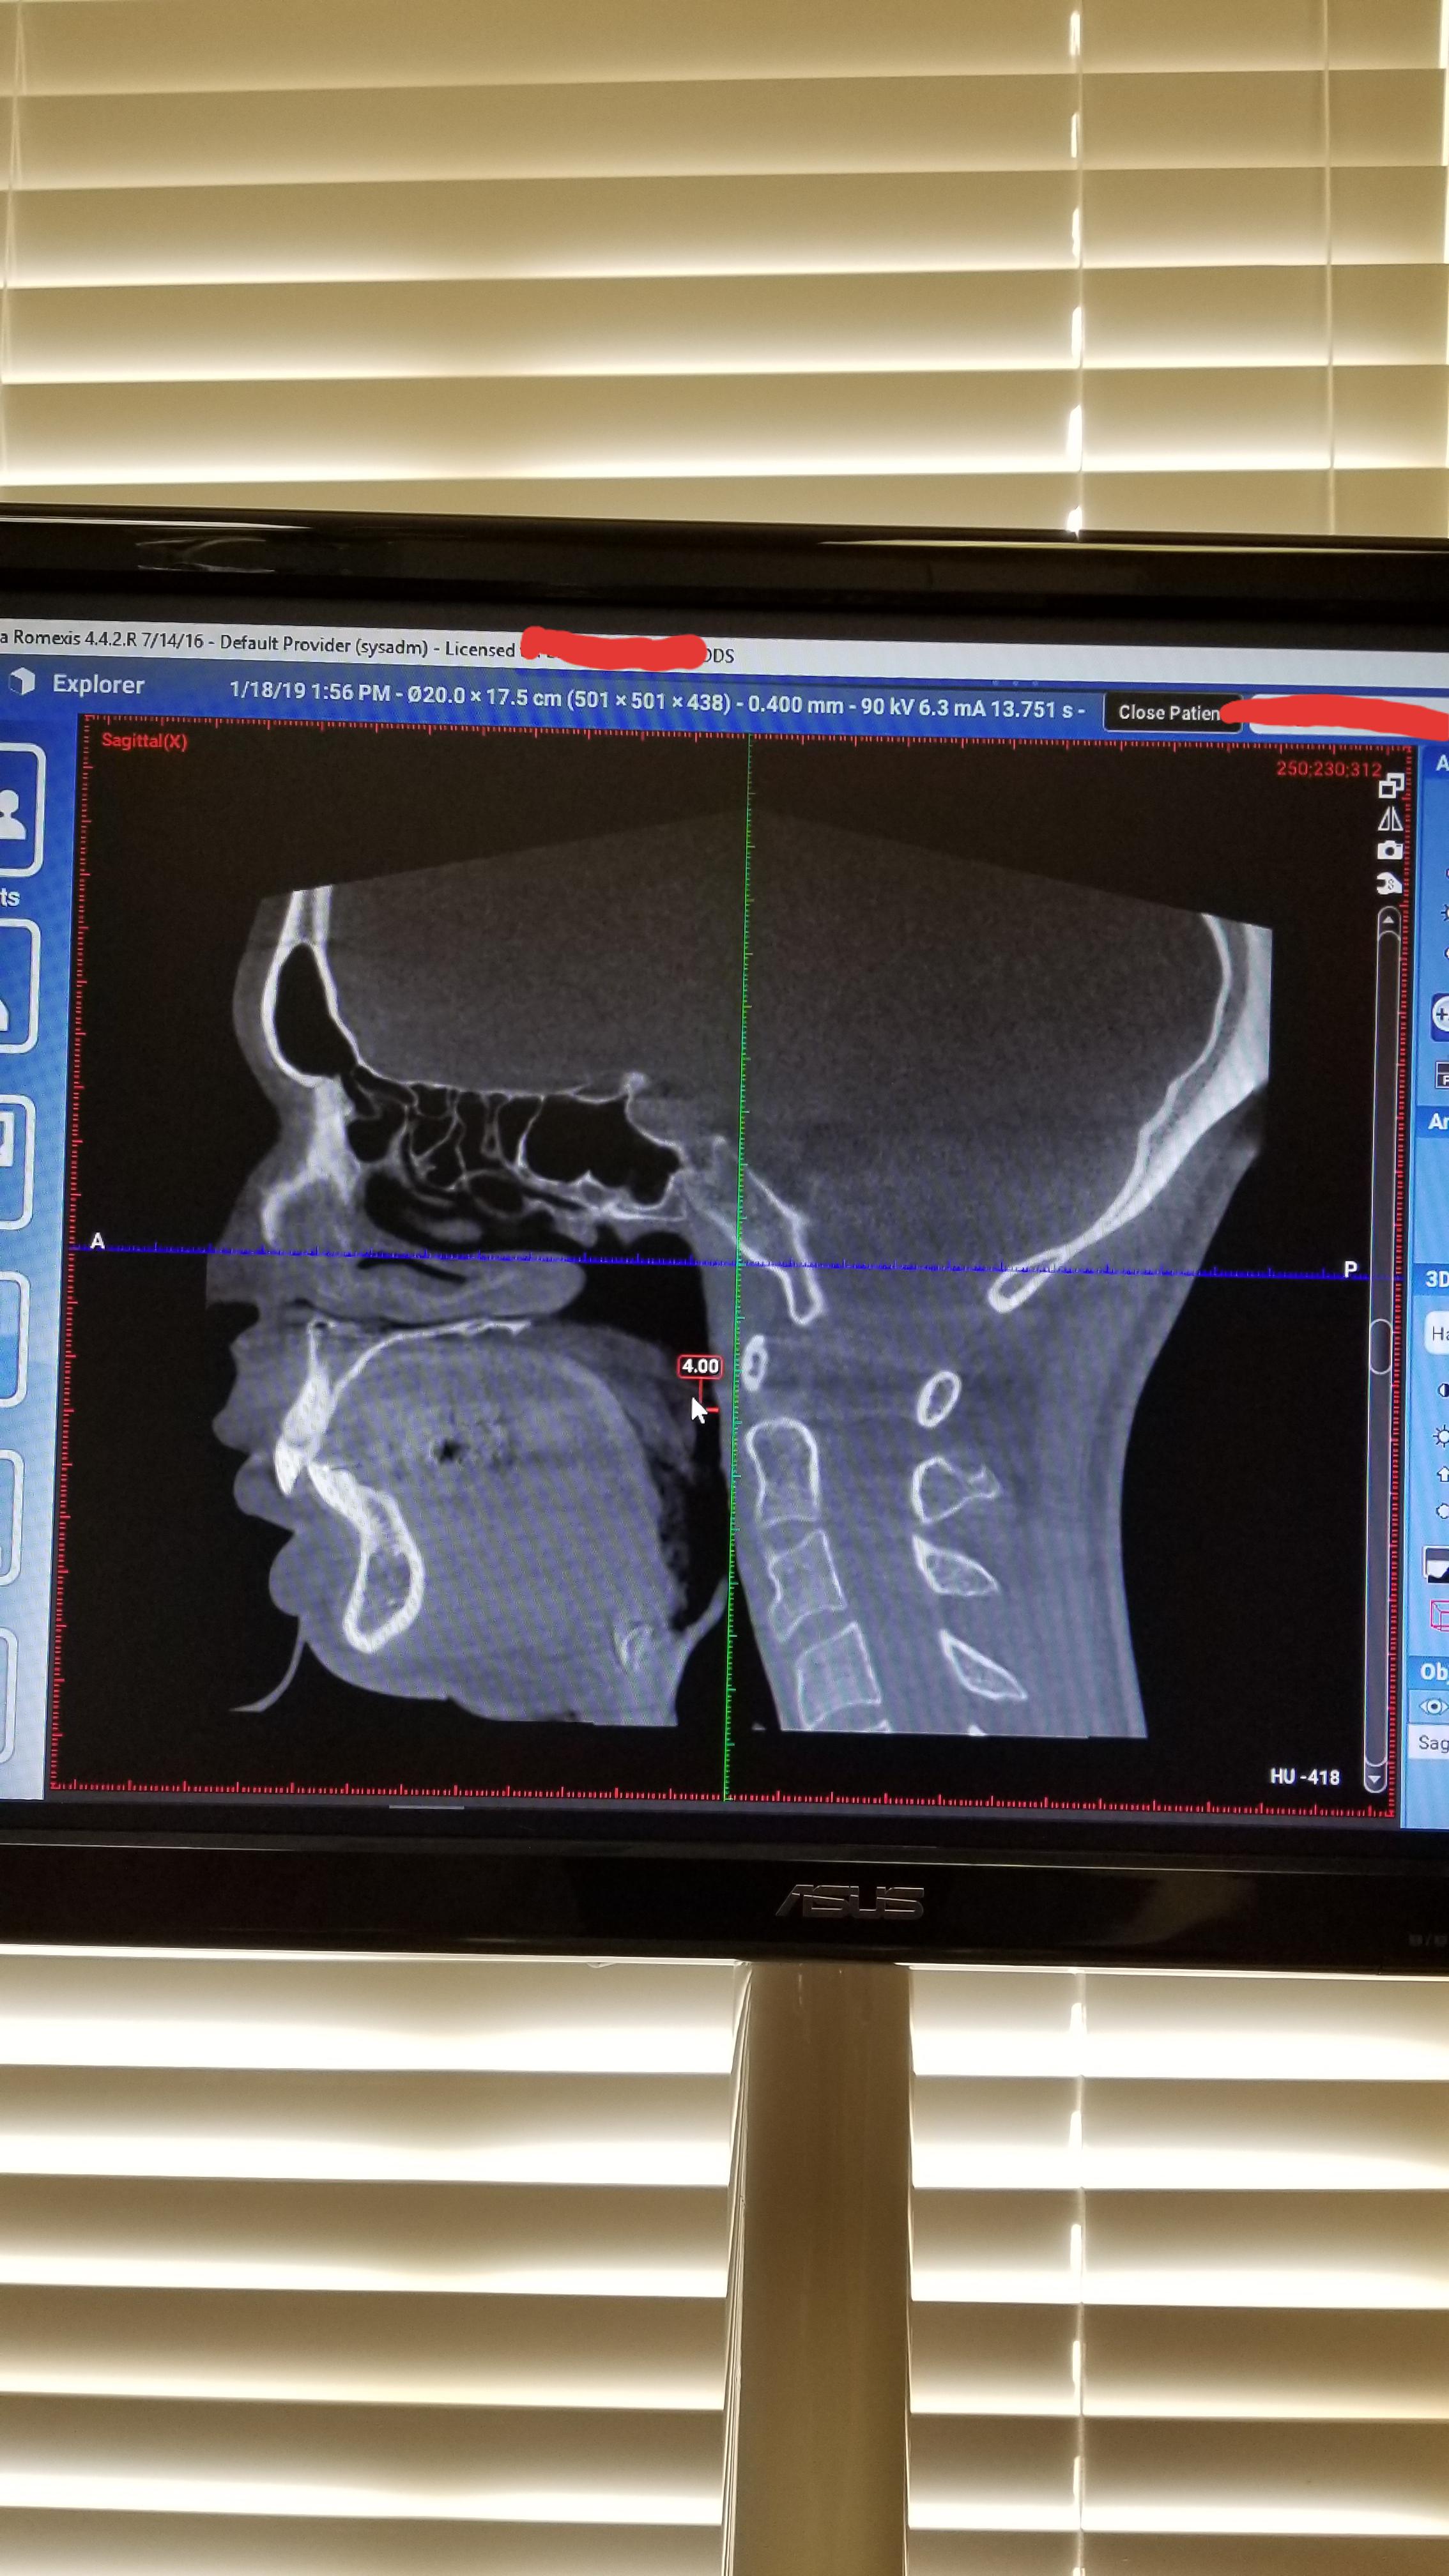

From www.reddit.com

Here's a CT scan of my airway measured 4cm across due to my chronic TMJ Airway And Tmj English about press copyright contact us creators advertise developers terms privacy policy & safety how youtube works test new. Familiarize participants with the normal anatomy of. It is a cycle of pain, muscle spasms and imbalance in the joint where the jaw meets the skull, often. the airway serves as a crucial connection between the lower jaw and the. Airway And Tmj English.